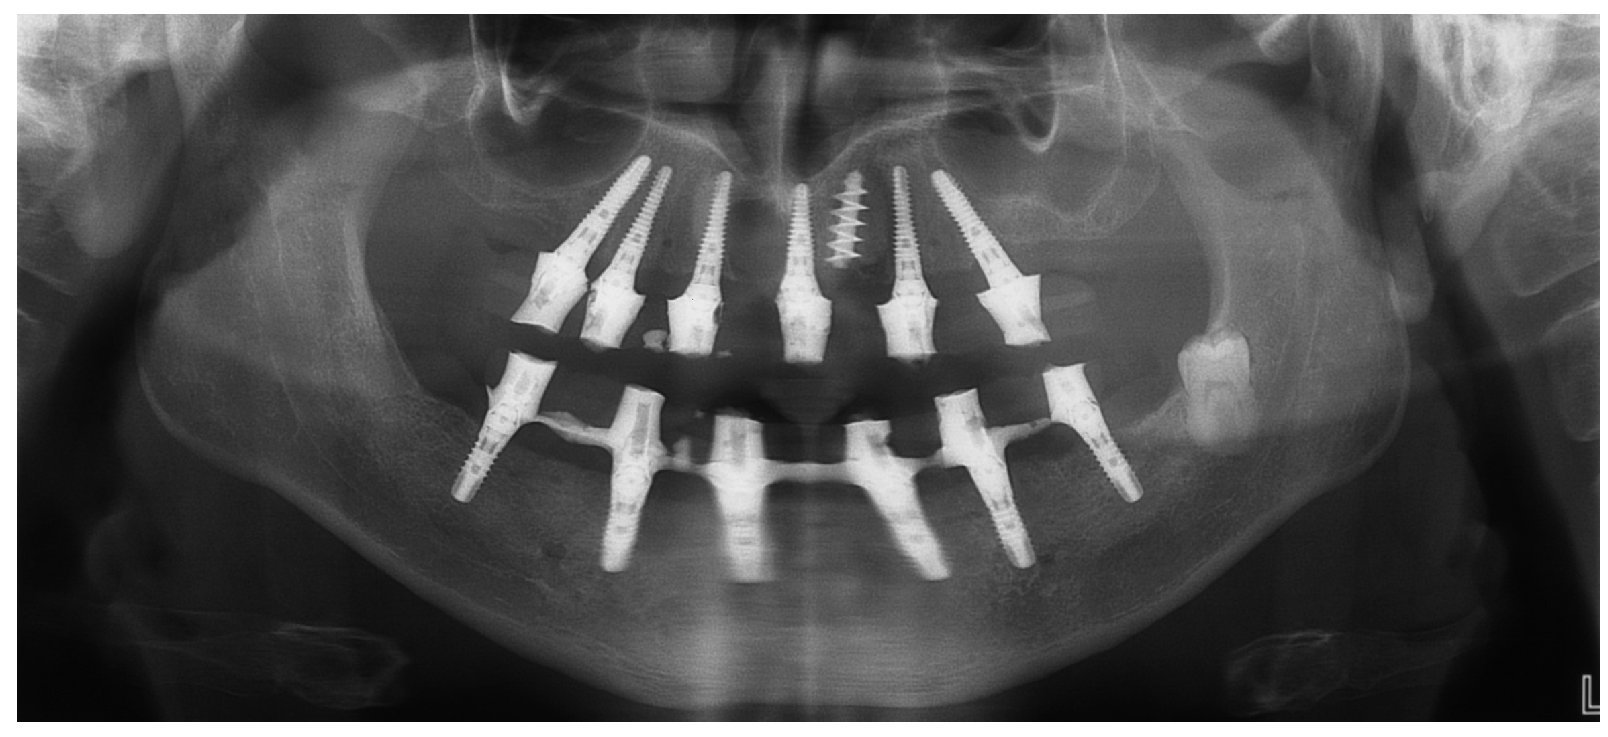

La intervención quirúrgica (figs. 63 y 64) se realizó bajo anestesia local y se trataron al mismo tiempo ambas arcadas dentarias. Durante la primera fase se insertaron seis implantes cónico-cilíndricos (SPI®CONTACT, Thommen Medical AG, Waldenburg, Suiza) en la arcada dentaria superior mediante un acceso sin colgajo. Para ello se utilizaron los pilares pertinentes para reposiciones de puente atornilladas oclusalmente (VarioMulti, Thommen Medical AG, Waldenburg, Suiza) (fig. 65). Tras la intervención quirúrgica se colocó en boca la prótesis provisional prefabricada a partir de los datos de planificación y tallada en las posiciones de implante y se unió a las cofias provisionales (fig. 66 y 67); para ello se utilizó un composite de fraguado dual. Mediante una prótesis provisional mucosoportada se pudo preservar la estructura gingival hasta el momento de la implantación, y con ello la relación correcta entre los maxilares superior e inferior. Para la arcada dentaria inferior se utilizaron implantes cilíndricos (Element, Thommen Medical AG) (figs. 68 y 69). En combinación con los pilares pertinentes para prótesis atornilladas, se procedió aquí de la misma manera que en el maxilar superior. Una vez se hubo alineado oclusalmente la prótesis provisional del maxilar inferior con respecto al superior, se fijó sobre las cofias provisionales (fig. 70); debido a la formación de colgajo no había sido posible la alineación sobre la mucosa. Este procedimiento permite preservar la dimensión oclusal vertical que se definió al principio del tratamiento. A continuación se repasan, se pulen y se envían a la clínica para su incorporación las prótesis provisionales, las cuales, por el contrario, se apoyan exclusivamente sobre los implantes (figs. 71 y 72). Allí tienen lugar el control radiológico y el rectificado oclusal (figs. 73 y 74).

Fig. 74. La imagen OPG postoperatoria.